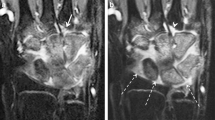

A large anatomy-based region of interest was manually drawn on the axial maximal enhancement maps by a radiology trainee (3 years of experience with imaging in JIA), while using the axial post-contrast T1-weighted dynamic contrast-enhanced MR image as a reference. The region of interest was drawn to exclude visible vessels, tendons and the epiphysis of the radius and ulna (Fig. 1) because no synovium was expected. The three most proximal and three most distal slices of the dynamic contrast-enhanced MRI suffered from fold-over artifacts and were therefore excluded from the analysis. To maintain a consistent field of view in every patient, the 20 slices distal to the last slice on which the ulna appeared were considered suitable for analysis of dynamic contrast-enhanced MRI.

Example of a manually drawn region of interest (white line) on the maximal enhancement map (left) based on axial wrist MRI in a 9-year-old female with clinically active juvenile idiopathic arthritis. The arrows indicate the arteries and vessels, which have not been included in the region of interest. A high spatial resolution T1-weighted image with fat saturation after intravenous contrast administration (right) is added for anatomical reference

The difference between clinically active juvenile idiopathic arthritis in an 8-year-old boy (left) and inactive juvenile idiopathic arthritis in a 13-year-old girl (right) on maximum enhancement maps (upper row), time-intensity-curve shape maps (middle row), and T1-weighted dynamic contrast-enhanced-maps (bottom row). The colors of the time-intensity-curve shapes correspond with the time-intensity-curve shapes as mentioned in Fig. 2. Scan parameters: axial plane, echo time 6.9 ms, repetition time 9.9 ms, voxel size 1.0 mm × 1.0 mm × 1.5 mm, temporal resolution 15.5 s